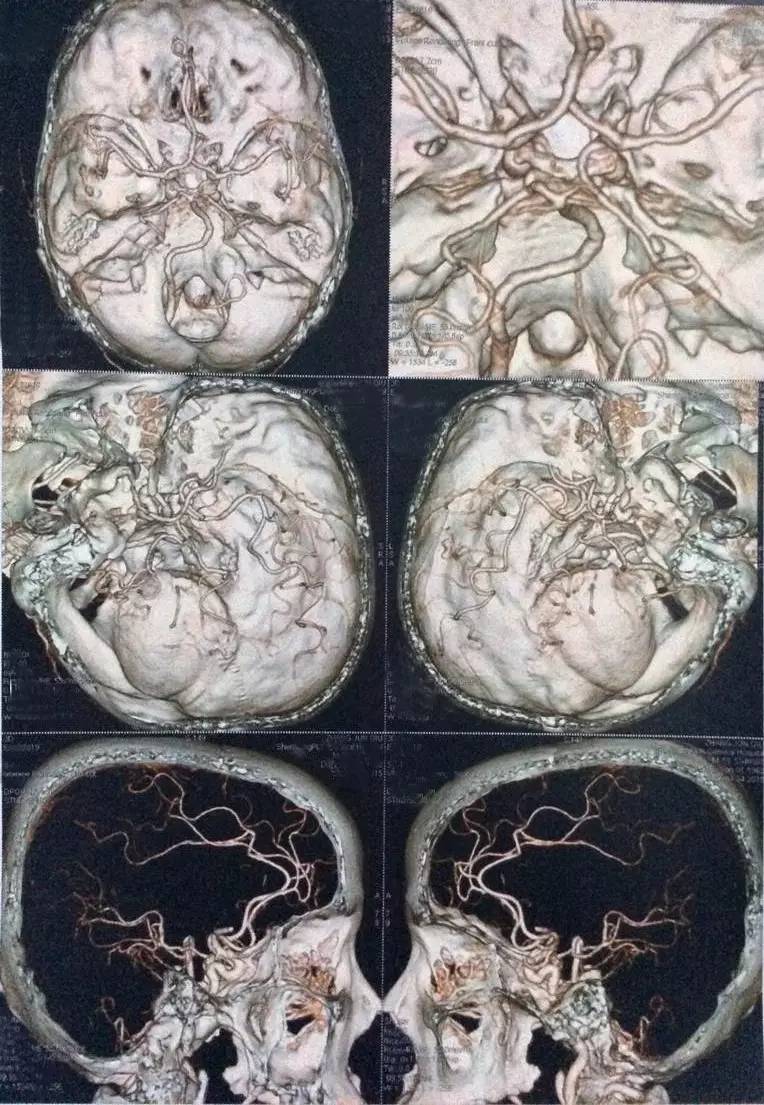

右侧椎动脉颅内段局限性显示纤细,余脑血管未见明显异常。

右颈内动脉近段混合斑块形成,管腔狭窄约20%;右椎动脉起始处非钙化斑块形成,管腔狭窄约40-50%,余颈部血管未见明显异常。